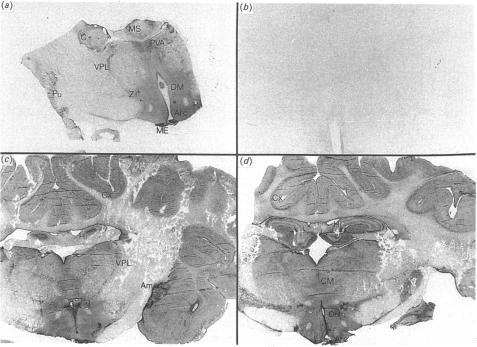

In this study we have solubilized and characterized binding sites for calcitonin (CT) from sheep brainstem. Autoradiography of 125I-labelled salmon CT (125I-sCT) binding to sheep diencephalon revealed a similar pattern of binding to that seen in other species, although the extent of distribution was greater in the sheep. CT binding activity could be extracted from membranes with either CHAPS or digitonin, but not with beta-octyl glucoside, 125I-sCT binding was saturable, with a dissociation constant for CHAPS-solubilized membranes of 2.8 +/- 0.5 nM and a maximum binding site concentration of 6.2 +/- 1.6 pmol/mg of protein. In competition binding studies, various CTs and their analogues demonstrated a similar rank order of potency to that seen in other CT receptor systems, Optimal binding occurred in the pH range 6.5-7.5, and was decreased in the presence of NaCl concentrations greater than 200 mM. In contrast with most other CT receptor binding systems, in which binding is poorly reversible, the binding of 125I-sCT to sheep brain binding sites underwent substantial dissociation upon addition of excess unlabelled sCT, with 40% and 46% dissociation after 2 h at 4 degree C in particulate and solubilized membranes respectively. Photoaffinity labelling of the binding site with the biologically active analogue 125I-[Arg11,18,4-azidobenzoyl-Lys14]sCT and analysis on SDS/PAGE under reducing conditions revealed a specific protein band of Mr approximately solubilized and particulate brain membranes. This is in accordance with the molecular size of CT receptors in other tissues where two species of receptor have been identified. one of Mr approximately 71,000 and another of Mr approximately 88,000. These results demonstrate the presence of high concentrations of CT binding sites in sheep brain which display different kinetic properties to those of CT receptors found in other tissues.